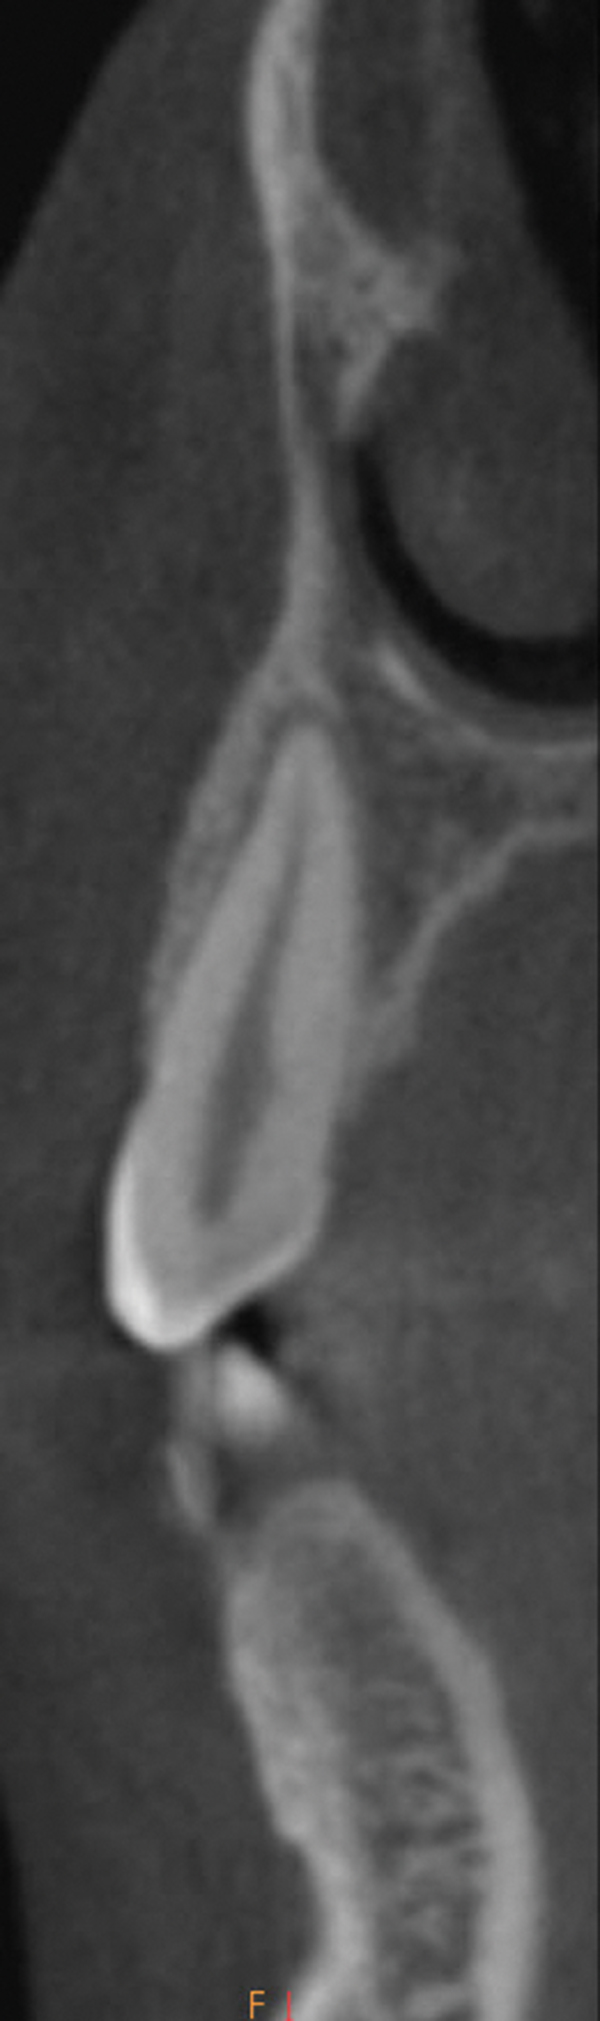

Fig 13 and Fig 14.

Pre- and post-SFOT dentoalveolar

bone presentation. Note the

facial bone augmentation and improved

incisor angle relationship.

Figure 13

Fig 13 and Fig 14. Pre- and post-SFOT dentoalveolar bone presentation. Note the

Figure 14